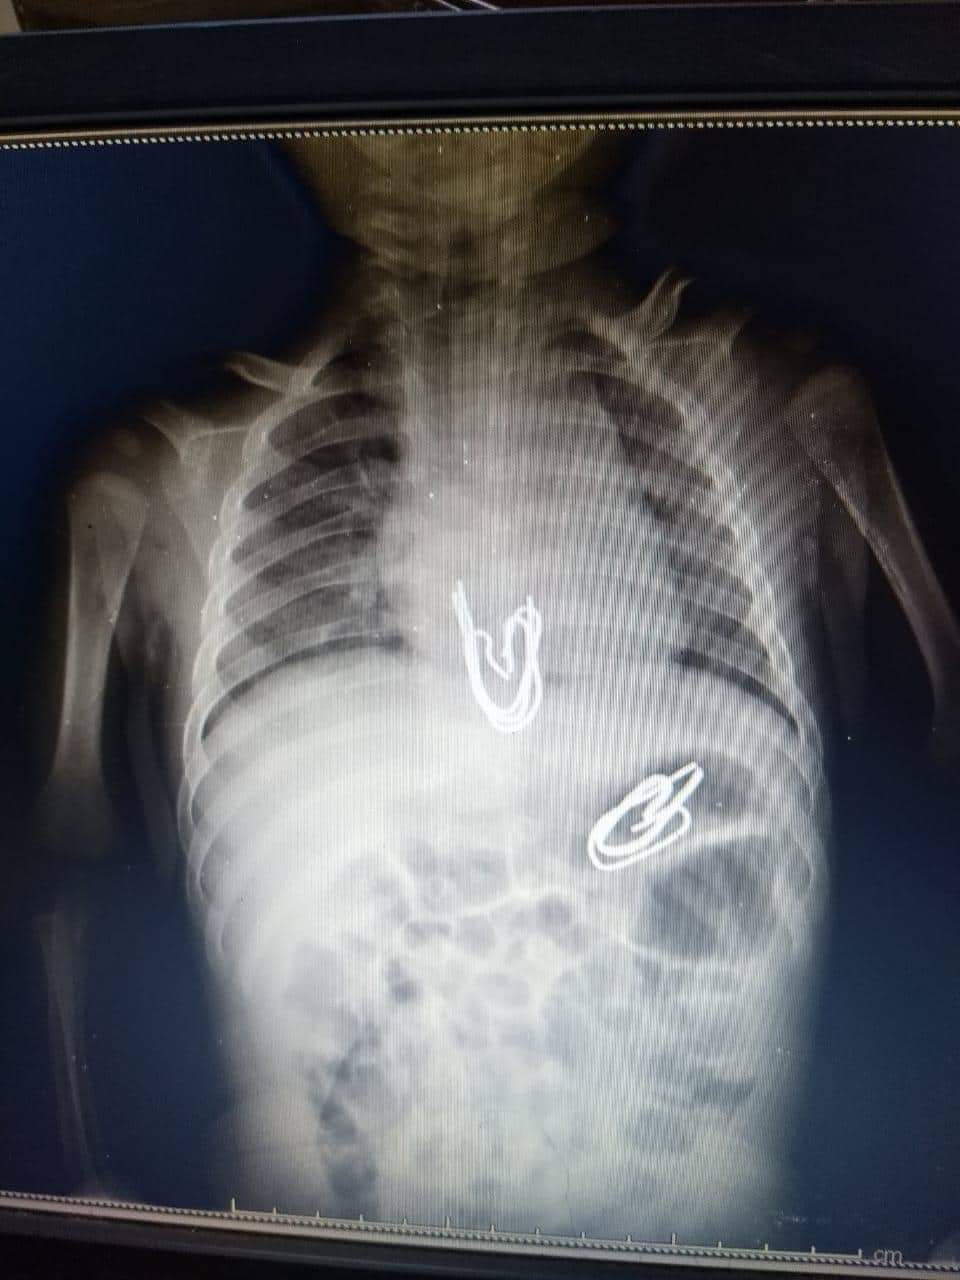

نجح فريق طبي بمستشفى الأطفال الجامعي بالمنصورة، من استخراج 5 دبابيس معدنية ابتلعها طفل يبلغ ثلاثة أشهر، من خلال إجراء عملية منظار معدة.

حيث تمكن فريق العمل بوحدة الجهاز الهضمي والكبد بمستشفي الأطفال الجامعي بالمنصورة، بقيادة الدكتور محمد عز، رئيس الوحدة، وبمساعدة الدكتوة دعاء فهمي، مدرس طب الأطفال، وقسم التخدير ممثلا في الدكتور أحمد عبد اللطيف، من إزالة 5 دبابيس معدنية يتراوح طول الدبوس الواحد حوالي 3 سم من مرئ ومعدة طفل يبلغ من العمر ثلاثة أشهر.

وأكدت الأم، أنها تركت طفلها الرضيع لفترة وجيزة مع أخته التي تبلغ 3 سنوات، وأخبرتها بأنها وضعت دبابيس معدنية تستخدم في تعليق الستائر داخل فم الطفل، وبعد عمل أشعة علي البطن تبين وجود مجموعة من الأجسام المعدنية في المرئ وأخرى في المعدة.

وأوضح الفريق الطبي، أن الأجسام المعدنية ذات أطراف حادة، وكان هناك تخوف من أن تكون قد جرحت جدار المعدة والمرئ، ما دفعهم لإجراء أشعة مقطعية أثبتت عدم وجود جروح.

وأضاف أنه بعد التشاور مع قسم جراحة الأطفال تحت قيادة الدكتور أدهم السعيد، ومساعدة الدكتور محمد البشبيشي، مدرس جراحة الأطفال، ونجح الفريق الطبي في عمل منظار معدة للطفل، واستخراج الدبابيس المعدنية بسلام.

وأشار الدكتور محمد عز، رئيس الوحدة، إلى أن هذه الحالة تعد من الحالات الصعبة نظرًا لعمر الطفل، ووجود عدد كبير من الدبابيس ذات الأطراف الحادة التي تحتاج لمهارة عالية في استخراجها.